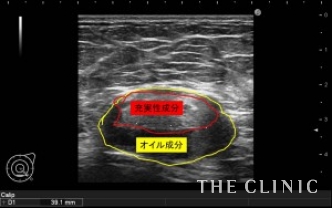

エコーにて、右にオイルシスト、左にオイルシストと4㎝の混合性腫瘤を認めました。(オイルシストの症例はNo.32でご紹介します)

混合性腫瘤の被膜が非常に硬く、中々カニューレが被膜を破れませんでした。何とか突き破ることが出来、ベイザーリポで崩していきます。

脂肪を崩して完全に吸引除去しました。